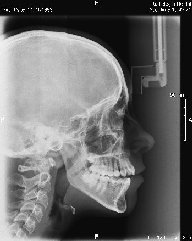

• Telerradiografía frontal y lateral digital

• Cefalometría computarizada

Algunos ejemplos de imágenes digitales

Pulse en las imágenes para ver la ampliación

fte